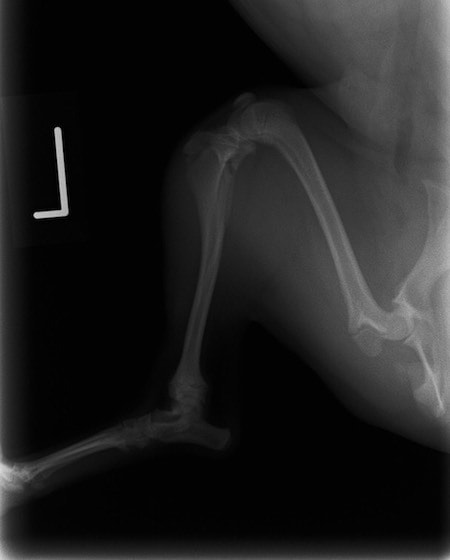

症例3:キルシュナーワイヤーのピンニングによる整復

ペルシャ猫 11ヶ月齢 雄

他院にて左大腿骨遠位の成長板骨折(salter-harrisⅠ型)が認められており、治療相談を目的として来院。当院にて、キルシュナーワイヤーを用いたピンニングにより骨折部位の整復を行いました。術後の経過は良好で、現在も経過観察中です。

術前レントゲン